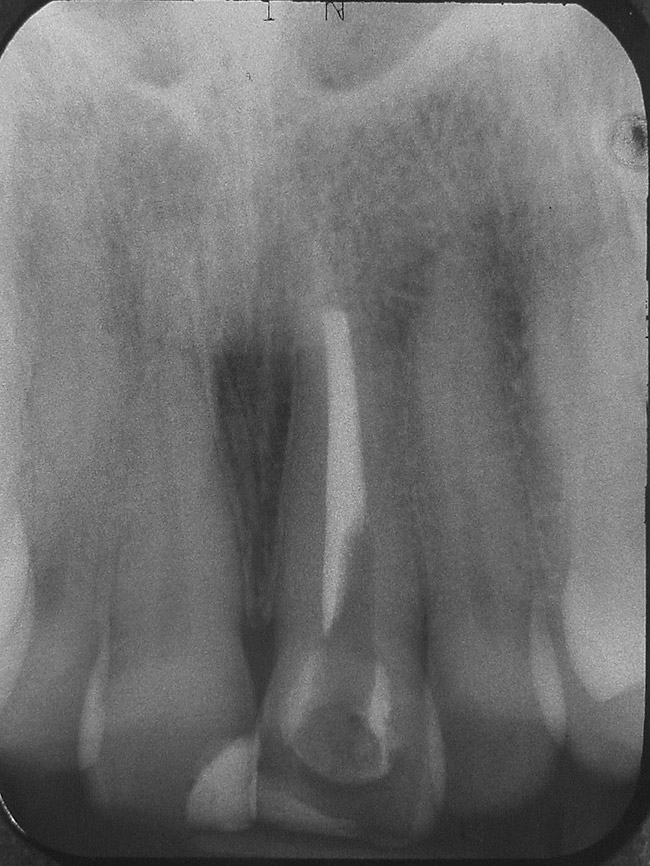

In some cases, the root canal is enlarged. This may be because of the need for endodontic treatment of a young anterior tooth because of trauma (Figure 7), a tooth that has had the root canal enlarged during endodontic treatment, or any tooth that has significant caries in the pulp chamber. For the young child, maintaining the tooth is critical and in some cases an apexification procedure is necessary. For an adult patient, treatment recommendations for an enlarged root canal or caries in the pulp chamber should include replacement with an implant. For the young, immature tooth where there is an enlarged root canal and the root and crown are at risk of fracture, an adhesive-resin cement can be used for root reinforcement. In a widely flared canal, the use of a clear, light-transmitting post with a fourth-generation etch-and-rinse adhesive and a light-cure composite is recommended. The technique with the light-transmitting post involves restoring the enlarged, overprepared root canal with an adhesive restorative composite resin with the post placed centered in the root canal. The post extends 2 mm from the canal and is light-cured at right angles for 1 to 2 minutes. The post is removed leaving a composite resin “canal” that can then be restored with either a prefabricated post or a custom-cast post-and-core. The composite reinforces the overflared canal (Figure 8A and Figure 8B).66-68

Figure 7  Immature central incisor fractured before completion of apexification. Note the enlarged, immature root canal.

Figure 7